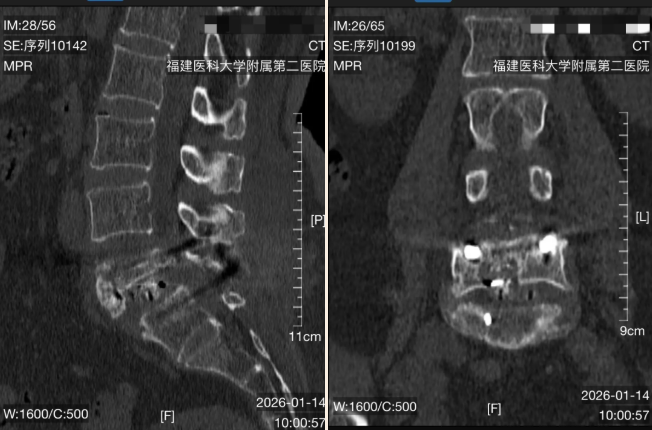

“真的可以吗?我手术两个月了,术后日夜疼痛一直卧床,已经准备坐一辈子轮椅了。”62岁的李阿姨(化名)被家人推入诊室时,眼里满是怀疑与疲惫。两个月前,她因腰椎滑脱在外院接受了手术,但严重的骨质疏松让内固定螺钉“抓不住”骨骼,导致内固定松动、融合器移位,持续的剧痛让她寸步难行。这不仅是李阿姨一个人的困境,更是老龄化社会中,严重骨质疏松患者面临手术挑战的缩影。...